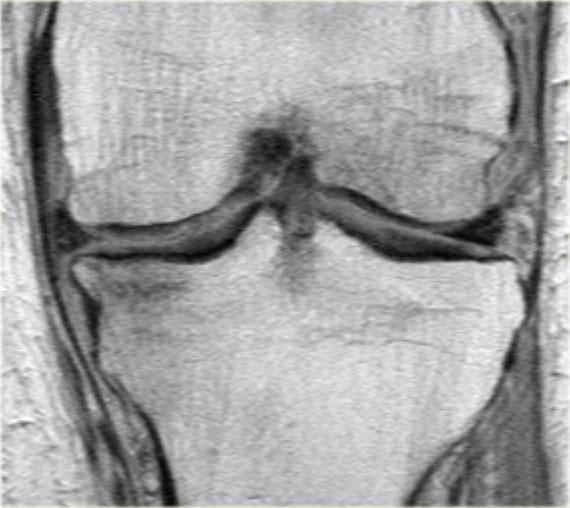

Ghi nhận một đường rách hướng tâm tại vị trí chân sụn chêm phía sau của sụn chêm trong, đường rách xuyên suốt toàn bộ chiều dày sụn chêm với hình ảnh khe dịch lan dọc theo khuyết tổn thương (mũi tên đỏ).

Rách chân sụn chêm thường đi kèm với hiện tượng thoát vị sụn chêm ra ngoài bờ mâm chày.

Thoát vị sụn chêm trên 3 mm thường liên quan đến các tổn thương rách tại vùng chân sụn chêm (6).

Trong trường hợp bên trái, ghi nhận một đường rách hướng tâm hoàn toàn tách rời sừng sau khỏi chân bám của nó (mũi tên đỏ).

Ngoài ra còn có hình ảnh thoát vị sụn chêm mức độ tối thiểu (hình 1/6).

Lưu ý rằng sừng sau không còn bám vào xương chày.

Thay vào đó, có thể thấy một khoảng hở (mũi tên cong).

Những tổn thương rách này rất dễ bị bỏ sót khi người đọc nhầm tưởng sừng sau vẫn bình thường.